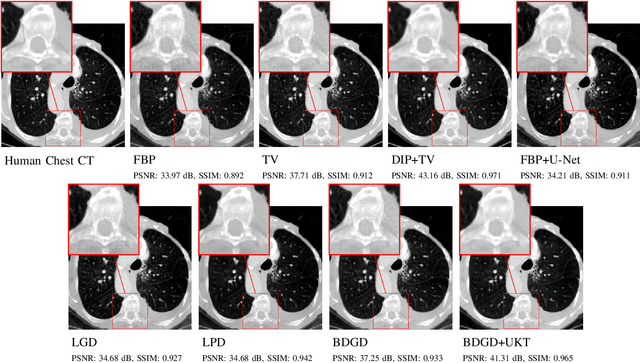

Abstract:Deep learning-based image reconstruction approaches have demonstrated impressive empirical performance in many imaging modalities. These approaches generally require a large amount of high-quality training data, which is often not available. To circumvent this issue, we develop a novel unsupervised knowledge-transfer paradigm for learned iterative reconstruction within a Bayesian framework. The proposed approach learns an iterative reconstruction network in two phases. The first phase trains a reconstruction network with a set of ordered pairs comprising of ground truth images and measurement data. The second phase fine-tunes the pretrained network to the measurement data without supervision. Furthermore, the framework delivers uncertainty information over the reconstructed image. We present extensive experimental results on low-dose and sparse-view computed tomography, showing that the proposed framework significantly improves reconstruction quality not only visually, but also quantitatively in terms of PSNR and SSIM, and is competitive with several state-of-the-art supervised and unsupervised reconstruction techniques.